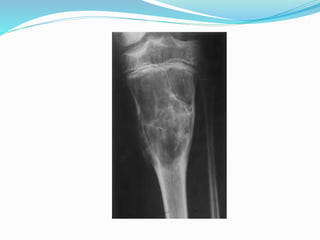

Plain X-ray

 An area of translucency centrally in the metadiaphysis

is characteristic.

 The overlying cortex is often thinned and slightly

expansed with no periosteal reaction unless a fracture

has occurred.

 Sclerotic reaction is usually present around the

margin.

 A serpiginous margin (by prominent ridges of bone)

may cause the cyst to appear multilocular.

Fallen fragment sign

 If there is fracture through this lesion, a dependent

bony fragment may be seen, and this is known as the

fallen fragment sign.

Plain X-ray  Anarea of translucency centrally in the metadiaphysis is characteristic.  The overlying cortex is often thinned and slightly expansed with no periosteal reaction unless a fracture has occurred.  Sclerotic reaction is usually present around the margin.  A serpiginous margin (by prominent ridges of bone) may cause the cyst to appear multilocular.

Fallen fragment sign If there is fracture through this lesion, a dependent bony fragment may be seen, and this is known as the fallen fragment sign.